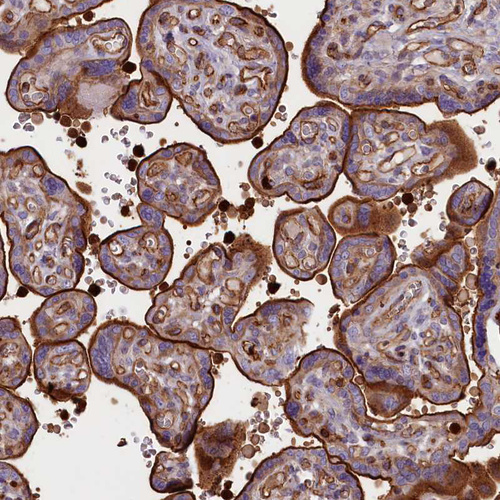

Immunohistochemical staining of human cerebral cortex shows strong membranous positivity in neuropil.